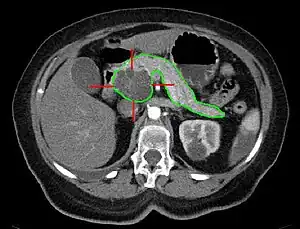

| MRI - cancerous pancreatic cyst | |

A pancreatic cyst is a fluid filled sac within the pancreas.[1] There are several types, some with the potential to become cancerous, and they are commonly found when investigating another problem.[2]

Up to one in five MRIs and 3% of CTs in older people may show a pancreatic cyst.[2] The most common pancreatic cysts are the serous cystadenoma, mucinous cystic neoplasm (MCN), and intraductal papillary mucinous neoplasm (IPMN).[2]